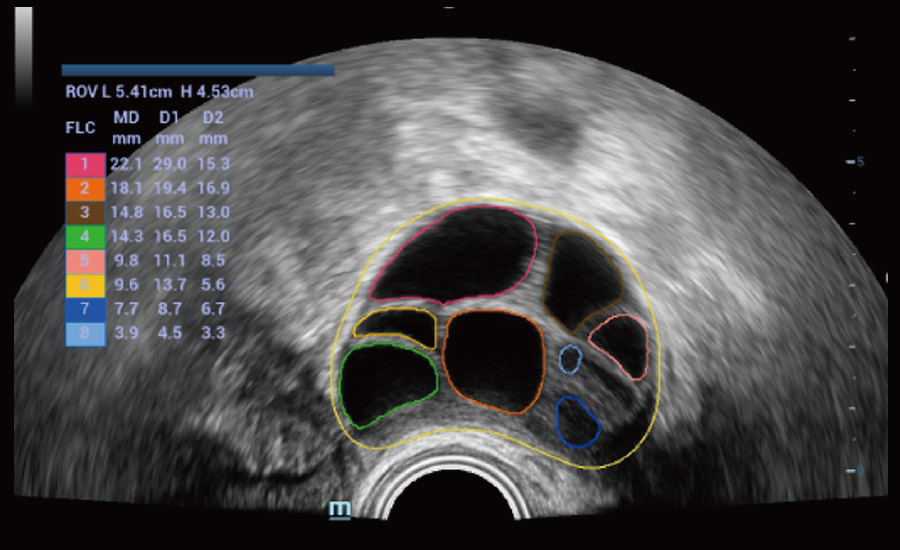

UMA (Ultra-Micro Angiography)

The innovative technology breaks the bottlenecks of traditional Doppler imaging. With ultra-high spatial resolution and flow sensitivity, it allows detecting super-subtle and super-slow flow perfusions, thereby extending the clinical application of qualitative and quantitative ultrasound evaluation in fetal brain, kidney, placenta, endometrium, ovary, etc.

3D UMA - perifollicular blood flow

Combining advanced algorithms and domain-specific knowledge, the innovative Smart Scene solution enables auto identification of tissue characteristics and provides organ-specific diagnosis with full-stack intelligence. Based on auto scenario identification, the solution not only realizes smart 2D scanning with auto settings and measurements, but also delivers 3D full-stack intelligence in every step from volume imaging optimization to the difficult 2D plane acquisition, and quantification throughout whole procedure. It helps a lot in reducing the dependency on clinical skills, while increasing diagnostic accuracy, confidence and efficiency.

Fertility